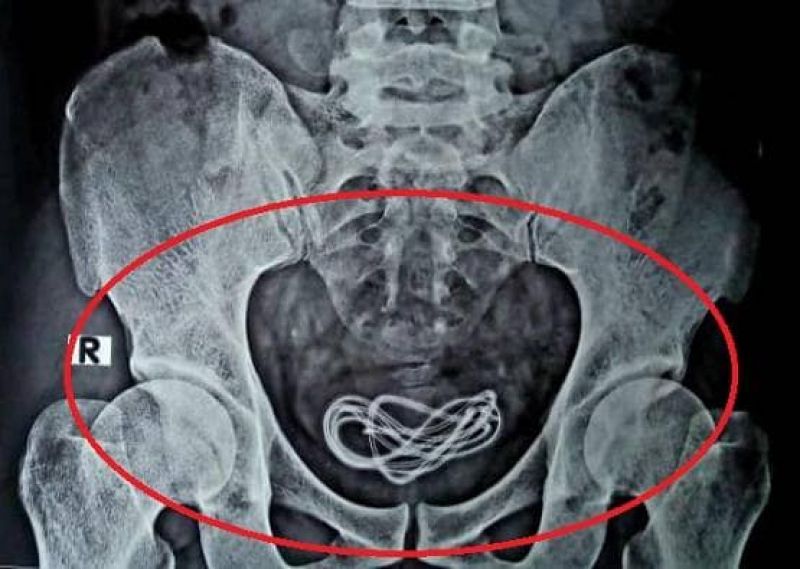

ਨਵੀਂ ਦਿੱਲੀ: ਕਈ ਵਾਰ ਹਸਪਤਾਲ ਵਿਚ ਦਾਖਲ ਮਰੀਜ਼ ਦੇ ਆਪ੍ਰੇਸ਼ਨ ਤੋਂ ਬਾਅਦ ਅਜਿਹੀਆਂ ਖ਼ਬਰਾਂ ਸਾਹਮਣੇ ਆਉਂਦੀਆਂ ਹਨ ਜੋ ਹਰ ਕਿਸੇ ਨੂੰ ਹੈਰਾਨ ਕਰ ਦਿੰਦੀਆਂ ਹਨ। ਅਜਿਹੀ ਹੀ ਇਕ ਘਟਨਾ ਅਸਾਮ ਦੇ ਗੁਹਾਟੀ ਤੋਂ ਸਾਹਮਣੇ ਆਈ ਹੈ, ਜਿਥੇ ਇਕ ਹਸਪਤਾਲ ਦੇ ਡਾਕਟਰ ਉਸ ਸਮੇਂ ਹੈਰਾਨ ਰਹਿ ਗਏ ਜਦੋਂ ਉਨ੍ਹਾਂ ਨੇ ਸਰਜਰੀ ਦੌਰਾਨ ਇਕ ਨੌਜਵਾਨ ਦੇ ਬਲੈਡਰ ਵਿਚੋਂ ਇਕ ਹੈੱਡਫੋਨ ਕੇਬਲ ਕੱਢਿਆ।

ਦਰਅਸਲ, ਇਸ ਘਟਨਾ ਦੀ ਵੀਡੀਓ ਅਤੇ ਕੁਝ ਫੋਟੋਆਂ ਉਸ ਡਾਕਟਰ ਨੇ ਖ਼ੁਦ ਸੋਸ਼ਲ ਮੀਡੀਆ 'ਤੇ ਸ਼ੇਅਰ ਕੀਤੀਆਂ ਹਨ। ਵੀਡੀਓ ਵਿਚ ਇਹ ਸਾਫ ਹੋ ਗਿਆ ਹੈ ਕਿ ਕਿਵੇਂ ਡਾਕਟਰ ਮਰੀਜ਼ ਦੇ ਪੇਟ ਵਿਚੋਂ ਕੇਬਲ ਕੱਢ ਰਹੇ ਹਨ। ਇਸ ਤੋਂ ਇਲਾਵਾ ਹੋਰ ਵੀ ਬਹੁਤ ਸਾਰੀਆਂ ਫੋਟੋਆਂ ਡਾਕਟਰ ਵੱਲੋਂ ਸਾਂਝੀਆਂ ਕੀਤੀਆਂ ਗਈਆਂ ਹਨ।

ਡਾਕਟਰ ਵਲੀ ਇਸਲਾਮ ਨੇ ਆਪਣੀ ਫੇਸਬੁੱਕ ਪੋਸਟ ਵਿਚ ਲਿਖਿਆ ਕਿ ਮੈਂ ਪਿਛਲੇ 25 ਸਾਲਾਂ ਤੋਂ ਸਰਜਰੀ ਕਰ ਰਿਹਾ ਹਾਂ, ਪਰ ਅਜਿਹਾ ਕੇਸ ਪਹਿਲੀ ਵਾਰ ਦੇਖਣ ਨੂੰ ਮਿਲਿਆ ਹੈ। ਉਨ੍ਹਾਂ ਦੱਸਿਆ ਕਿ ਇਕ ਵਿਅਕਤੀ ਉਨ੍ਹਾਂ ਕੋਲ ਆਇਆ ਅਤੇ ਉਸ ਨੇ ਦੱਸਿਆ ਕਿ ਉਸ ਨੇ ਗਲਤੀ ਨਾਲ ਹੈੱਡਫੋਨ ਕੇਬਲ ਨੂੰ ਨਿਗਲ ਲਿਆ ਹੈ।

ਮਰੀਜ ਕੁਝ ਹਫ਼ਤੇ ਪਹਿਲਾਂ ਹੀ ਡਾਕਟਰ ਕੋਲ ਗਿਆ ਅਤੇ ਪੇਟ ਦਰਦ ਦੀ ਸ਼ਿਕਾਇਤ ਦੱਸੀ। ਇਸ ਤੋਂ ਬਾਅਦ ਡਾਕਟਰ ਨੇ ਉਸ ਨੌਜਵਾਨ ਦਾ ਅਪਰੇਸ਼ਨ ਕੀਤਾ ਅਤੇ ਕੇਬਲ ਨੂੰ ਬਾਹਰ ਕੱਢਿਆ। ਇਸ ਮਾਮਲੇ ਦੇ ਸਾਹਮਣੇ ਆਉਣ ਤੋਂ ਬਾਅਦ ਲੋਕ ਵੀ ਹੈਰਾਨ ਰਹਿ ਗਏ ਹਨ।